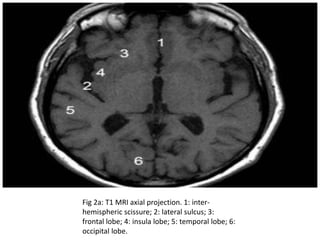

Fig 2a: T1 MRI axial projection. 1: inter-

hemispheric scissure; 2: lateral sulcus; 3:

frontal lobe; 4: insula lobe; 5: temporal lobe; 6:

occipital lobe.

Fig 2a: T1MRI axial projection. 1: inter- hemispheric scissure; 2: lateral sulcus; 3: frontal lobe; 4: insula lobe; 5: temporal lobe; 6: occipital lobe.